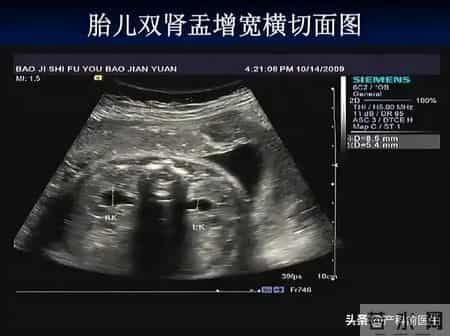

胎儿肾盂集合系分离,指的是:胎儿肾脏内部用于汇集尿液的结构(肾盂和集合系统)出现扩张。在超声上表现为:肾盂内径增宽,尿液暂时潴留。

本质上,这是一个影像学描述,并不是一个明确的疾病诊断。